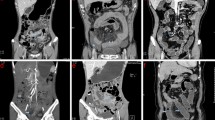

A tube current of 400 mA was used if the patient weight was less than 70 kg. Tube current was changed to 600 mA if the patient weight was more than 70 kg. Images were acquired using a 40 × 0.625 mm collimation, a 0.5-s rotation time, and pitch/speed of 1.375:1/55. Images were reconstructed on axial and coronal planes. CTE studies were transferred through the picture archiving computer system (PACS) to a workstation (AW Server, GE Healthcare, WI, USA). Using the Gemstone Spectral Imaging (GSI) viewer application, scans were reconstructed at VMI energy levels including 40 keV, 50 keV, 60 keV, 70 keV, 80 keV, 90 keV, 100 keV, and 110 keV (Fig. 1).

For patients with CD, abnormal or diseased bowel wall was radiologically identified when hyperenhancement of the bowel mucosa or bowel wall thickening were demonstrated [4, 12]. Qualitatively, mural hyperenhancement was determined by visual assessment of segmental hyperenhancement of the bowel wall comparing with the adjacent bowel loop with similar degree of distension. Quantitatively, hyperenhancement was evaluated using a diseased to non-diseased bowel loop enhancement ratio of more than 1.3 [4]. Two separate circular regions of interest (ROI) (area, 0.5 cm2) were placed within the diseased intestinal wall. A third ROI (area, 0.5 cm2) was placed within the gluteal muscle groups (Fig. 2). The ROI was placed away from tissue planes, intramuscular fat or calcifications as much as possible. A mean bowel attenuation was calculated from the AV that were obtained using two separate ROIs within the bowel wall. The standard deviation of the mean AV in the ROI represented the noise. The signal-to-noise ratio (SNR) and contrast-to-noise ratio (CNR) were calculated for each dataset at each VMI from 40 to 110 keV. SNR was measured by dividing the mean AV of the diseased intestinal wall by the mean background noise. CNR was defined as the HU difference between the mean AV of the diseased bowel wall and gluteal muscle divided by the mean noise of the muscle.

Measurement of attenuation from bowel wall and gluteal muscle. Two circular regions of interest (ROI) (area 0.5 cm2) were placed within the diseased intestinal walls and the mean was obtained (one ROI placed within the diseased bowel wall is not shown in the figure). Another ROI (area, 0.5 cm2) was placed within the gluteal muscle

The difference between affected and non-affected bowel walls of patients with CD at each reconstructed VMI for AV, SNR, and CNR are presented in Table 1. AV, SNR, and CNR were detected to be higher in diseased bowel walls than non-diseased bowel walls (Fig. 3). The difference between the abnormal and normal intestinal walls of CD patients in terms of attenuation, SNR, and CNR were statistically significant at each energy level of VMI (p < 0.001).

VMI at 40 keV provided the best AV for bowel wall despite the increased noise in our study. Additionally, for the subjective analysis for image quality and mural enhancement, VMI at 40 keV and 70 keV were helpful to radiologists in the evaluation of patients with CD. In our study, VMI at a high-energy level like 110 keV did not make a significant difference for the assessment of bowel walls of CD patients. It might be attributed to the progressively increased noise at a rate that is inversely proportional to the energy separation between the low- and high-energy spectra [18, 20, 27]. This is also observed at VMI at energy levels lower than 60 keV; however, VMI at lower energy levels might contribute more effectively to the diagnosis of mural enhancement compared to VMI at higher energy levels.